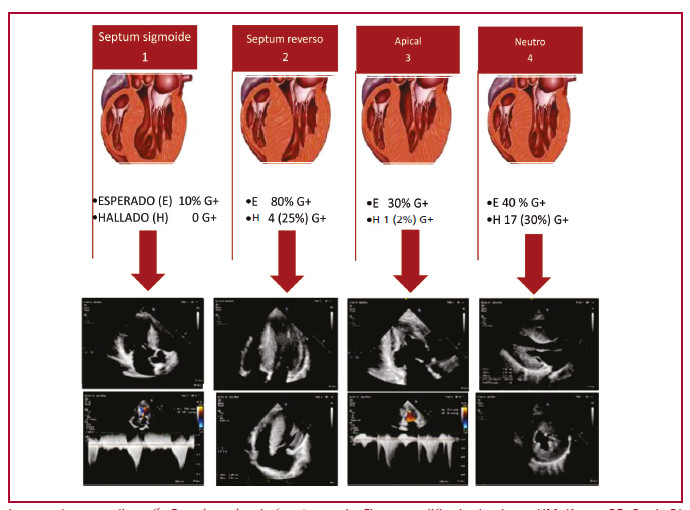

Para la descripción de las características fenotípicas se utilizó la clasificación de Maron con los cuatro fenotipos clásicos, según la ubicación y el grado de hipertrofia. 14

Para correlacionar fenotipo (F) con genotipo (G) se utilizó la clasificación de Lever que permite evaluar la probabilidad pretest según subtipo anatómico. 15

La clasificación de Lever 2 y 4 (septum reverso y neutro, respectivamente) resultó de gran utilidad a la hora de valorar la probabilidad de presentar un G+ basado en el fenotipo (F) anatómico expresado por el paciente (Tabla 2 y Figura 4).

Imagen de ecocardiografía Doppler color de fuente propia. Figura modificado de : Lever HM, Karam RF, Currie PJ, Healy BP. Hypertrophic cardiomyopathy in the elderly. Distinctions from the Young based on cardiac shape. Circulation 1989; 79(3):580-9.

Esta clasificación ha resultado de gran utilidad a la hora de valorar la probabilidad de presentar un estudio genético positivo basado en el fenotipo anatómico expresado por el paciente, en lo que se ha venido a llamar estudio genético guíado por ecocardiografía.

Modificado de: Lever HM, Karam RF, Currie PJ, Healy BP. Hypertrophic cardiomyopathy in the elderly. Distinctions from the young based on cardiac shape. Circulation 1989 Mar; 79(3):580-9.